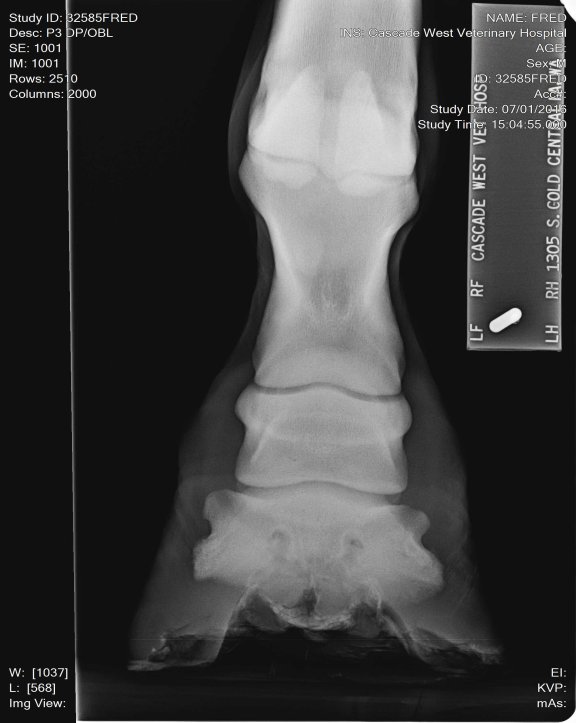

Location: Washington | So we got a young, 3 yr old, horse from some friend to break, put some time on and sale for them. AWESOME little horse with a nice cowbred pedigree. Our 7 yr old was riding him his 14th ride, he now has about 45 days on him. She's now taken over the reins working cows and trail riding. He's had a pretty easy life, no injuries or illness. We started advertising and have LOTS of interest BUT he has failed two pre purchase exams for lameness on the flex test. First was front left yesterday was front right. First vet check took X rays, he said he was clean, vet that looked at him yesterday said no, high ringbone! He rides sound but wont pass the flex tests. What are your expereinces with this? What are our options? Maintence?Β Β We WILL be up front and honest with his condition to potenial buyers but I'd like to know other peoples opinions and your most successful treatments.

Location: Lost in the swamps | My opinion these X rays don't look bad. I don't see any involvement in the joint spaces. I've seen a lot worse. He's got really long toes, you need to show your farrier these x rays and have him shorten and round his toes to quicken his break over is very important for horses dealing with ringbone. long toes create a lot of torque! This can also lead to lamine inflammation. The p-1 and p-2 is a low motion joint so it can actually fuse and the horse still have soundness. Your p2 and coffin joint is where you don't want any issues of ring bone. And I don't see any there. The upper pattern has some oddity near the seasmoid bone. Just curious did your vet mention anything? |